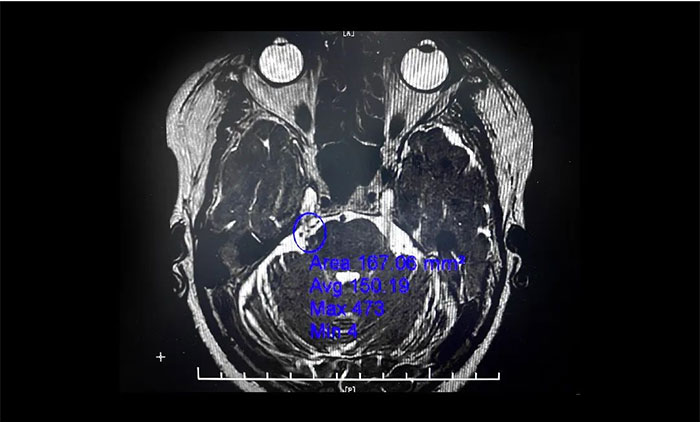

▲ 右侧三叉神经与周围小血管关系密切